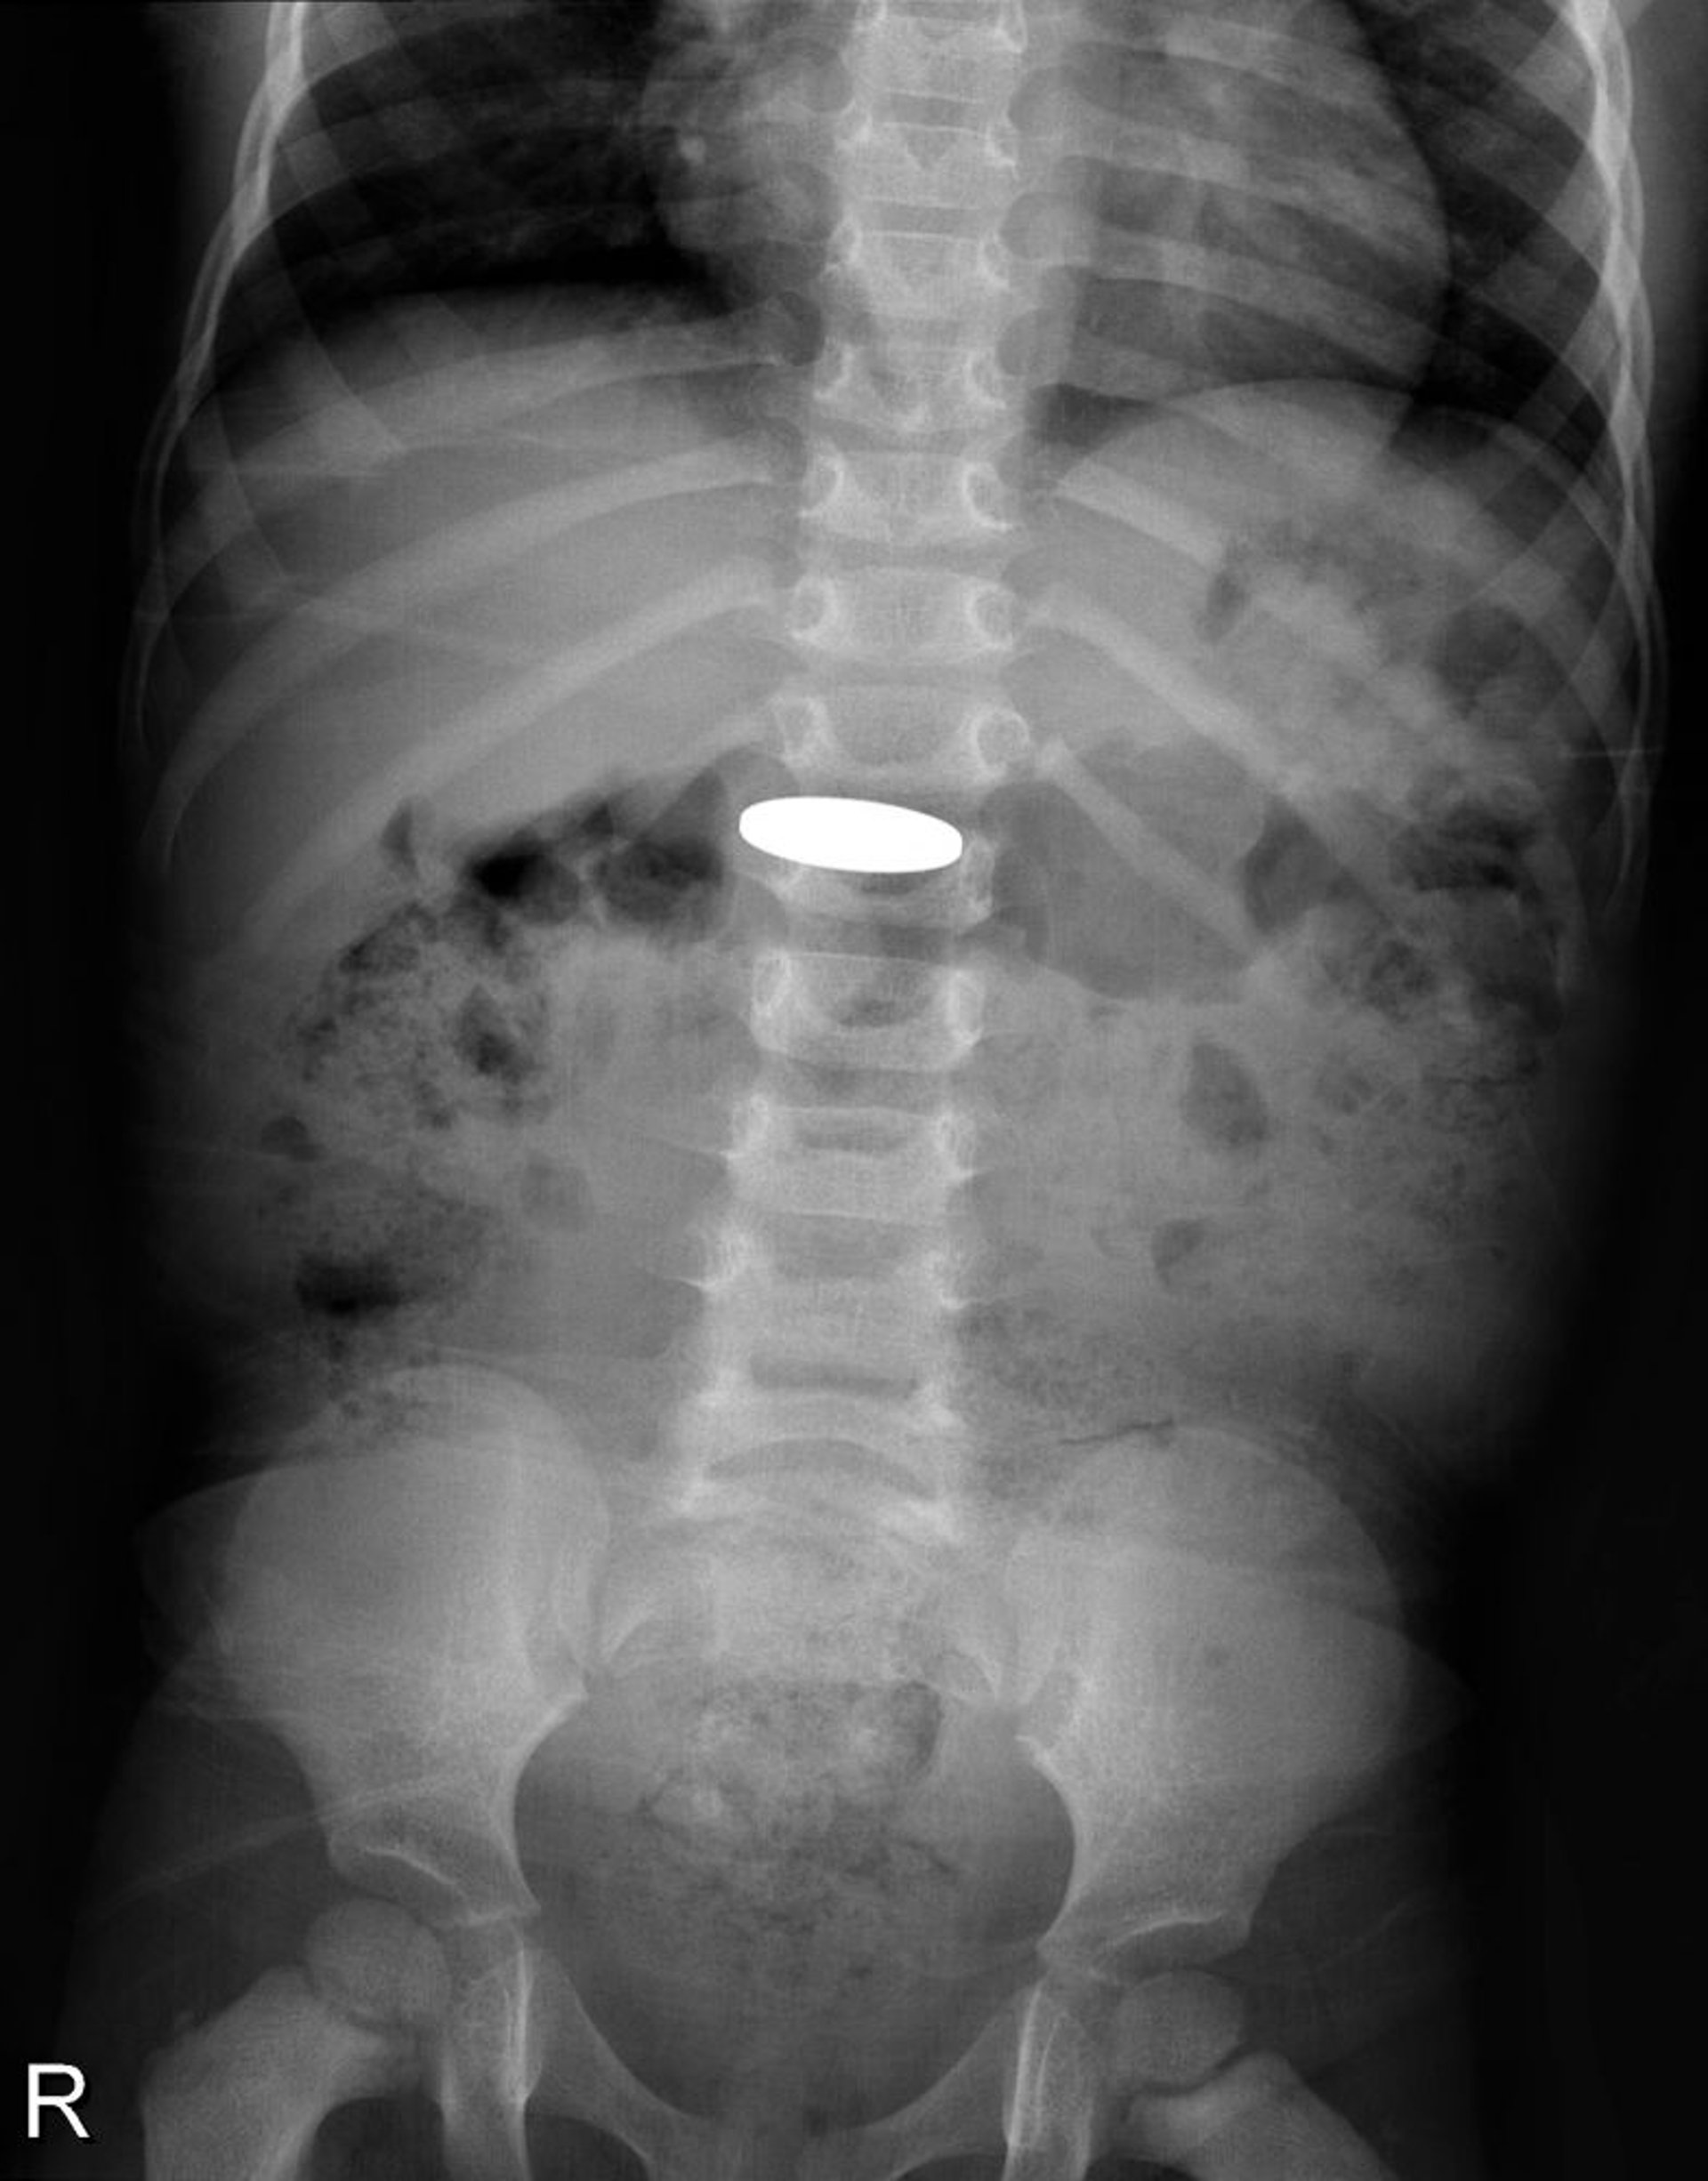

Corps étranger dans le tube digestif (radiographie)

Cette radiographie montre une pièce de monnaie avalée par un jeune enfant.